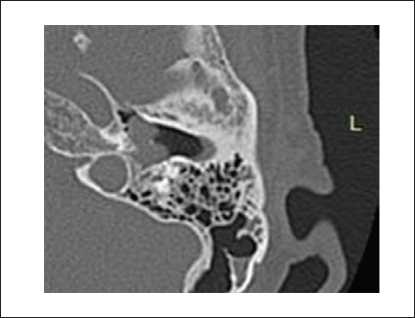

Пациенты первой группы также предъявляли жалобы на снижение слуха, при этом пареза лицевого нерва не отмечалось. При отоскопии у пациентов определялось бордовое образование за барабанной перепонкой. По данным лучевых исследований, на КТ височных костей у пациентов определялся мягкотканный субстрат, частично заполняющий барабанную полость (рисунок 1). На снимках МРТ головного мозга с контрастированием новообразование в барабанной полости активно накапливало контраст (рисунок 2).

Рисунок 1. КТ левой височной кости, аксиальная проекция. Параганглиома, тип А: барабанная полость заполнена мягкотканным субстратом, деструкция луковицы яремной вены не определяется.

Пациенты третьей группы с диагностированной распространенной параганглиомой предъявляли жалобы на отсутствие слуха с пораженной стороны, периодическое онемение лица, периодические эпизоды кровотечения из слухового прохода. У 6 пациентов, которые до поступления в нашу клинику неоднократно подвергались хирургическим вмешательствам, отмечался парез лицевого нерва со стороны поражения, который соответствовал 5–6 степени по шкале House – Brackmann. При отоскопии у пациентов определялось выпирающее в просвет наружного слухового прохода красно-бордовое пульсирующее объемное образование. По данным лучевых исследований, на КТ височных костей у пациентов определялся мягкотканный субстрат, заполняющий барабанную полость. Крыша барабанной полости была истончена, местами не определялась (1). Костная стенка канала внутренней сонной артерии не прослеживалась. На уровне луковицы яремной вены определялось мягкотканное образование, которое разрушало костные стенки гипотимпанума (2) (рисунок 5).

Рисунок 5. КТ правой височной кости, аксиальная проекция. Параганглиома, тип С: задняя стенка нижнечелюстной ямки местами не определяется (1). На уровне яремной ямки определяется мягкотканное содержимое, которое разрушает костные стенки гипотимпанума (2).